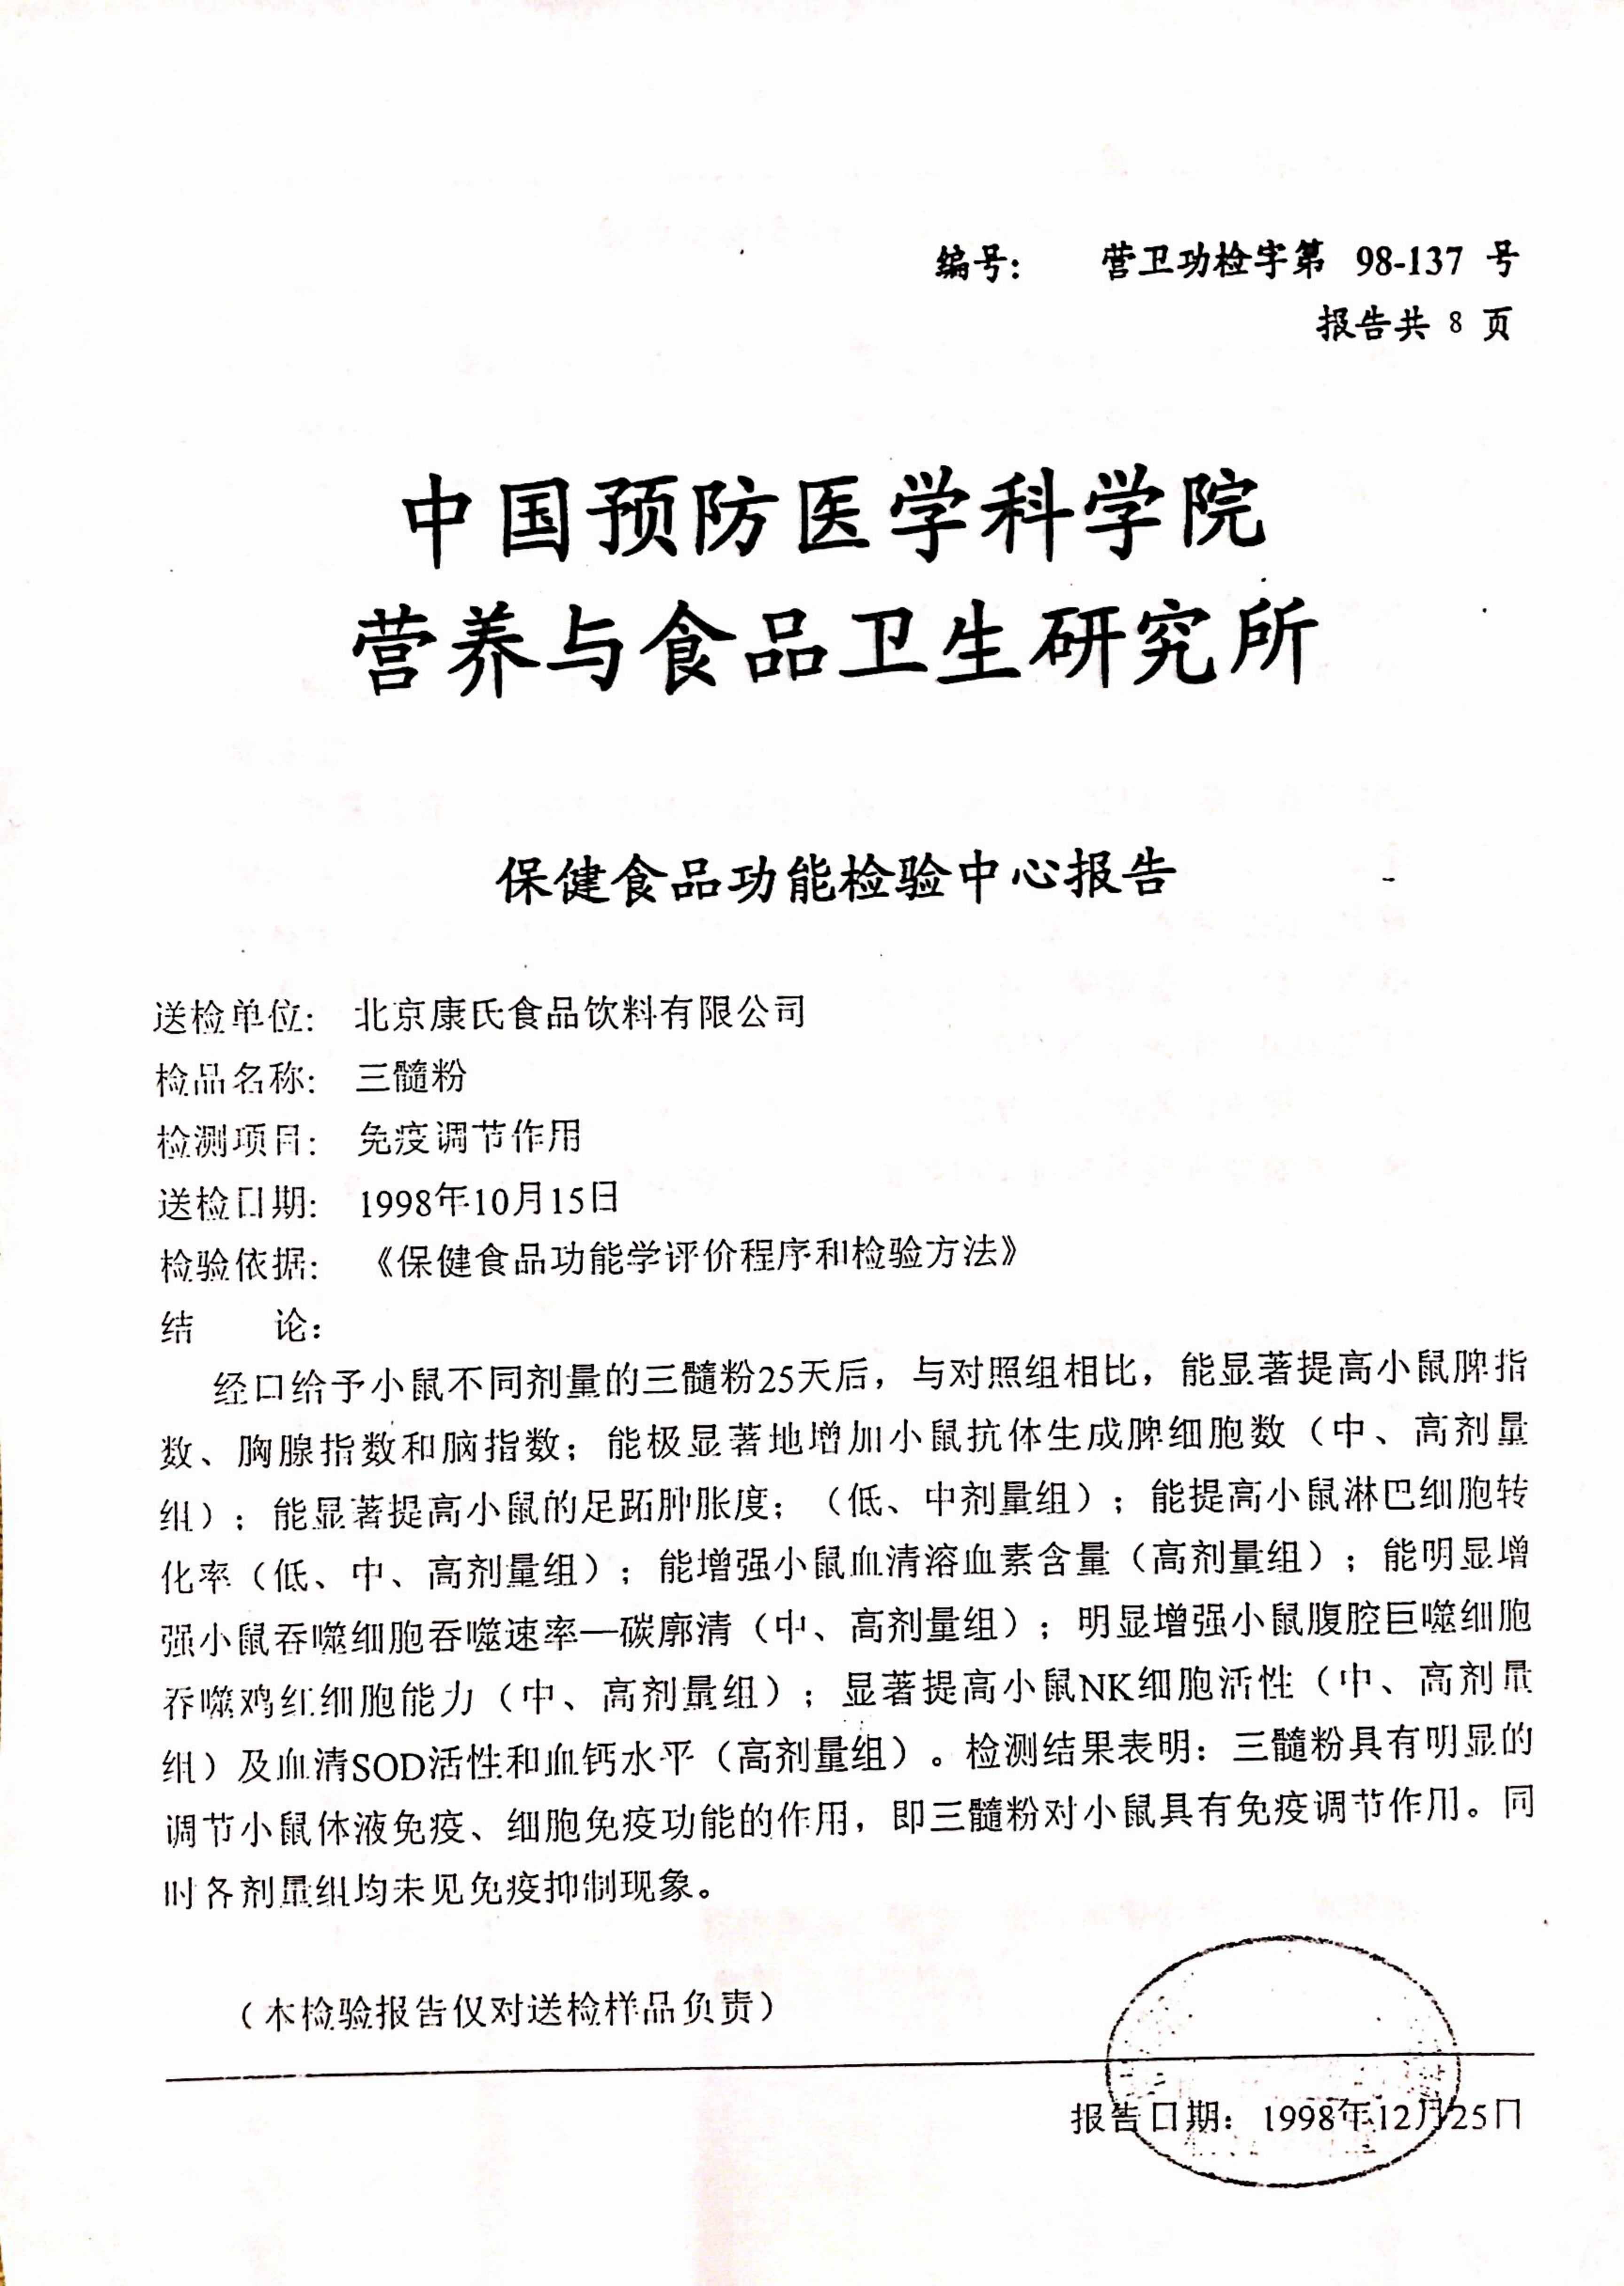

七项免疫功能检验报告